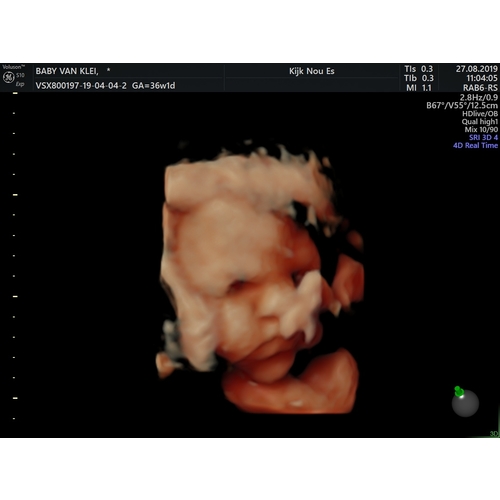

Guo is een vervroegde 20 weken echo wat geavanceerdere apparatuur. Ik zou heel goed aangeven dat je weet dat er extra risico’s aan kleven maar dat je nu als je dat kan opbrengen gezond eet bewust eet. Mocht je zo mondig zijn gewoon zeggen dat ze op moeten houden. Ik was er ook heel bang voor maar bij mij 1x de risico’s genoemd en daarna niet meer. Wel extra controle maar voel mij er niet vervelend door. Kindje gaat alles goed. Mijn suiker test was ook goed dus ook geen zwangerschaps diabetes en tot nu toe ben nu 28+2 900 gr aangekomen. eerst 2 kilo afgevallen doordat ik anders ben gaan eten. Het is enorm lastig en ja ik heb ook de neiging om zoet en snack te pakken maar weersta het het is al zo lastig om het er af te krijgen! Dus daarna was mijn insteek is het niet makkelijker dus ik weerhoud mijzelf. Foto’s is 20,24 en 28 weken heb je een idee☺️